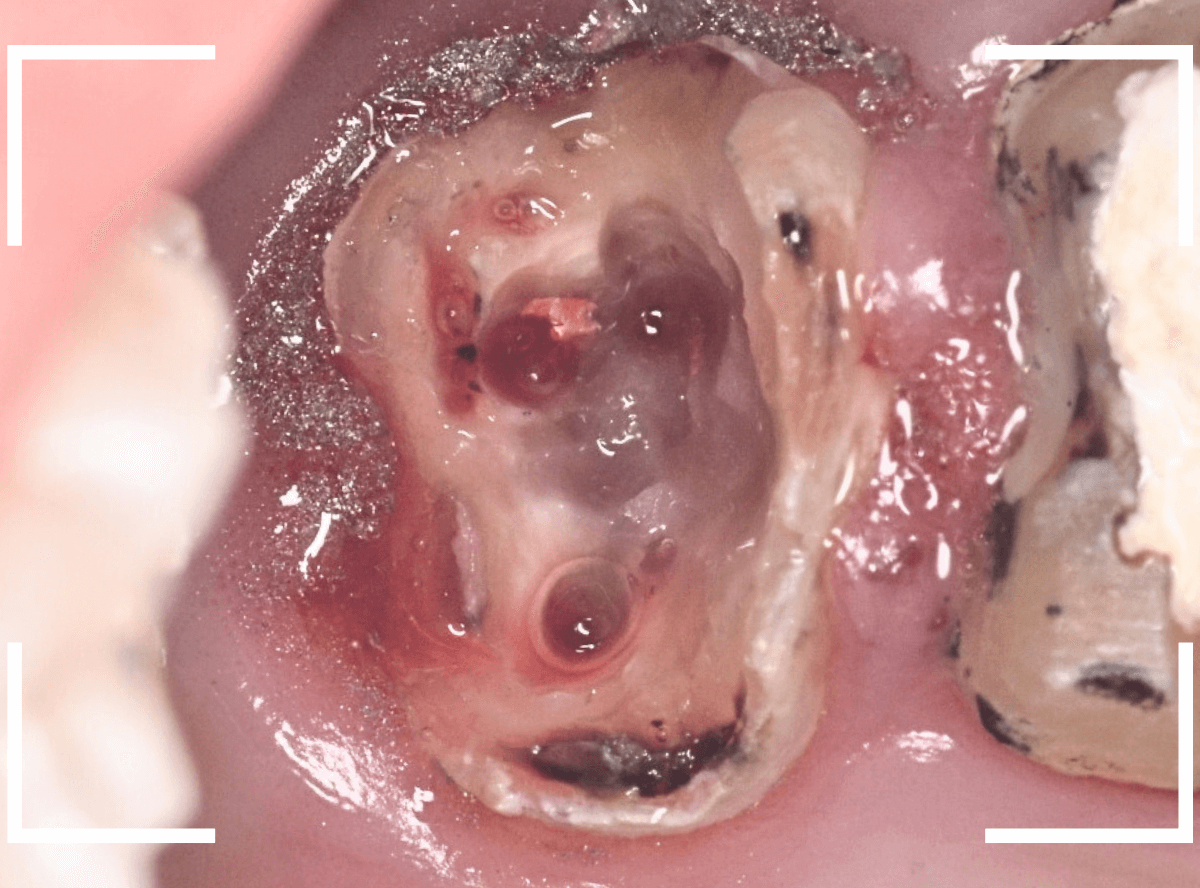

次は左側のメタルコアを除去します。

メタルコアをある程度除去したところです。

予想したとおり、中は少し虫歯になっていました。

写真ですとわかりづらいですが、青い部分の歯肉が歯の部分を覆ってしまっています。

このまま土台を作り直しても、短期間で土台ごとさし歯が外れてしまう可能性があがってしまいますので、麻酔をして余分な歯肉を除去する処置をします。

歯を覆っていた歯肉、虫歯、歯の根に残っていたピンを全て外しました。

相当な時間がかかりましたが、何とか歯を傷つける事なく処置ができました。